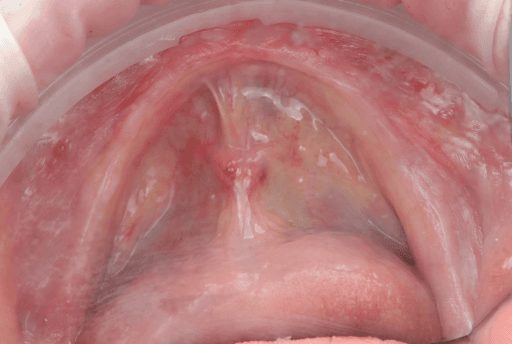

Upper arch pre-surgical intraoral situation

Upper arch surgical procedure. From left to right: Pre-surgical intraoral situation, 3D printed surgical guide with fixation pins, and seven implants placed.